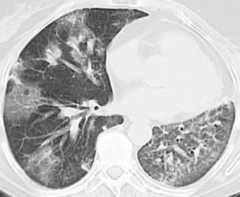

Typical HRCT pattern of UIP. The image shows subpleural and basal predominance of reticular opacities associated with traction bronchiectasis and honeycomb change (clustered cystic airspaces with well-defined thick walls and diameter of 0.3–1.0 cm)

Image: “(HRCT) pattern” by Interstitial Lung Disease Unit, Royal Brompton and Harefield NHS Foundation Trust, London, UK. License:CC BY 4.0